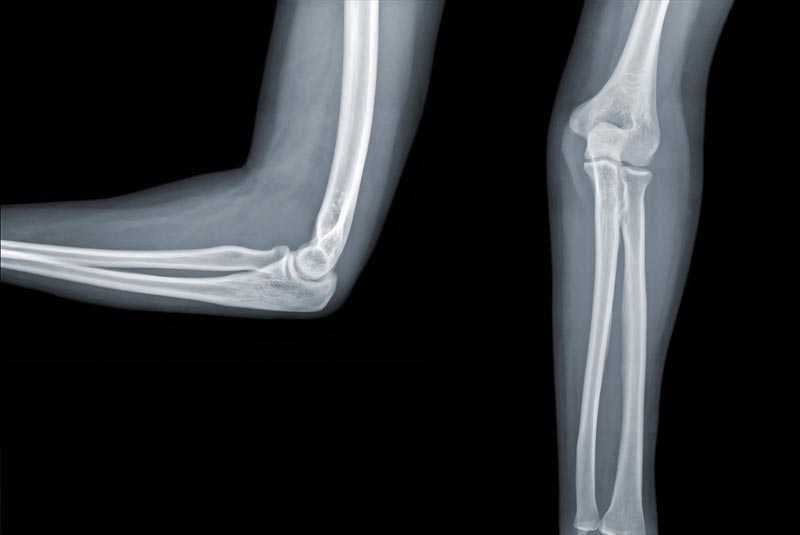

• Open Elbow Surgery (Tennis Elbow/Golfer’s Elbow release, Cubital Tunnel Decompression, Distal Biceps Tendon Repair, Elbow Dislocation/Instability, Olecranon Bursitis Excision)

• Elbow Fracture Fixation